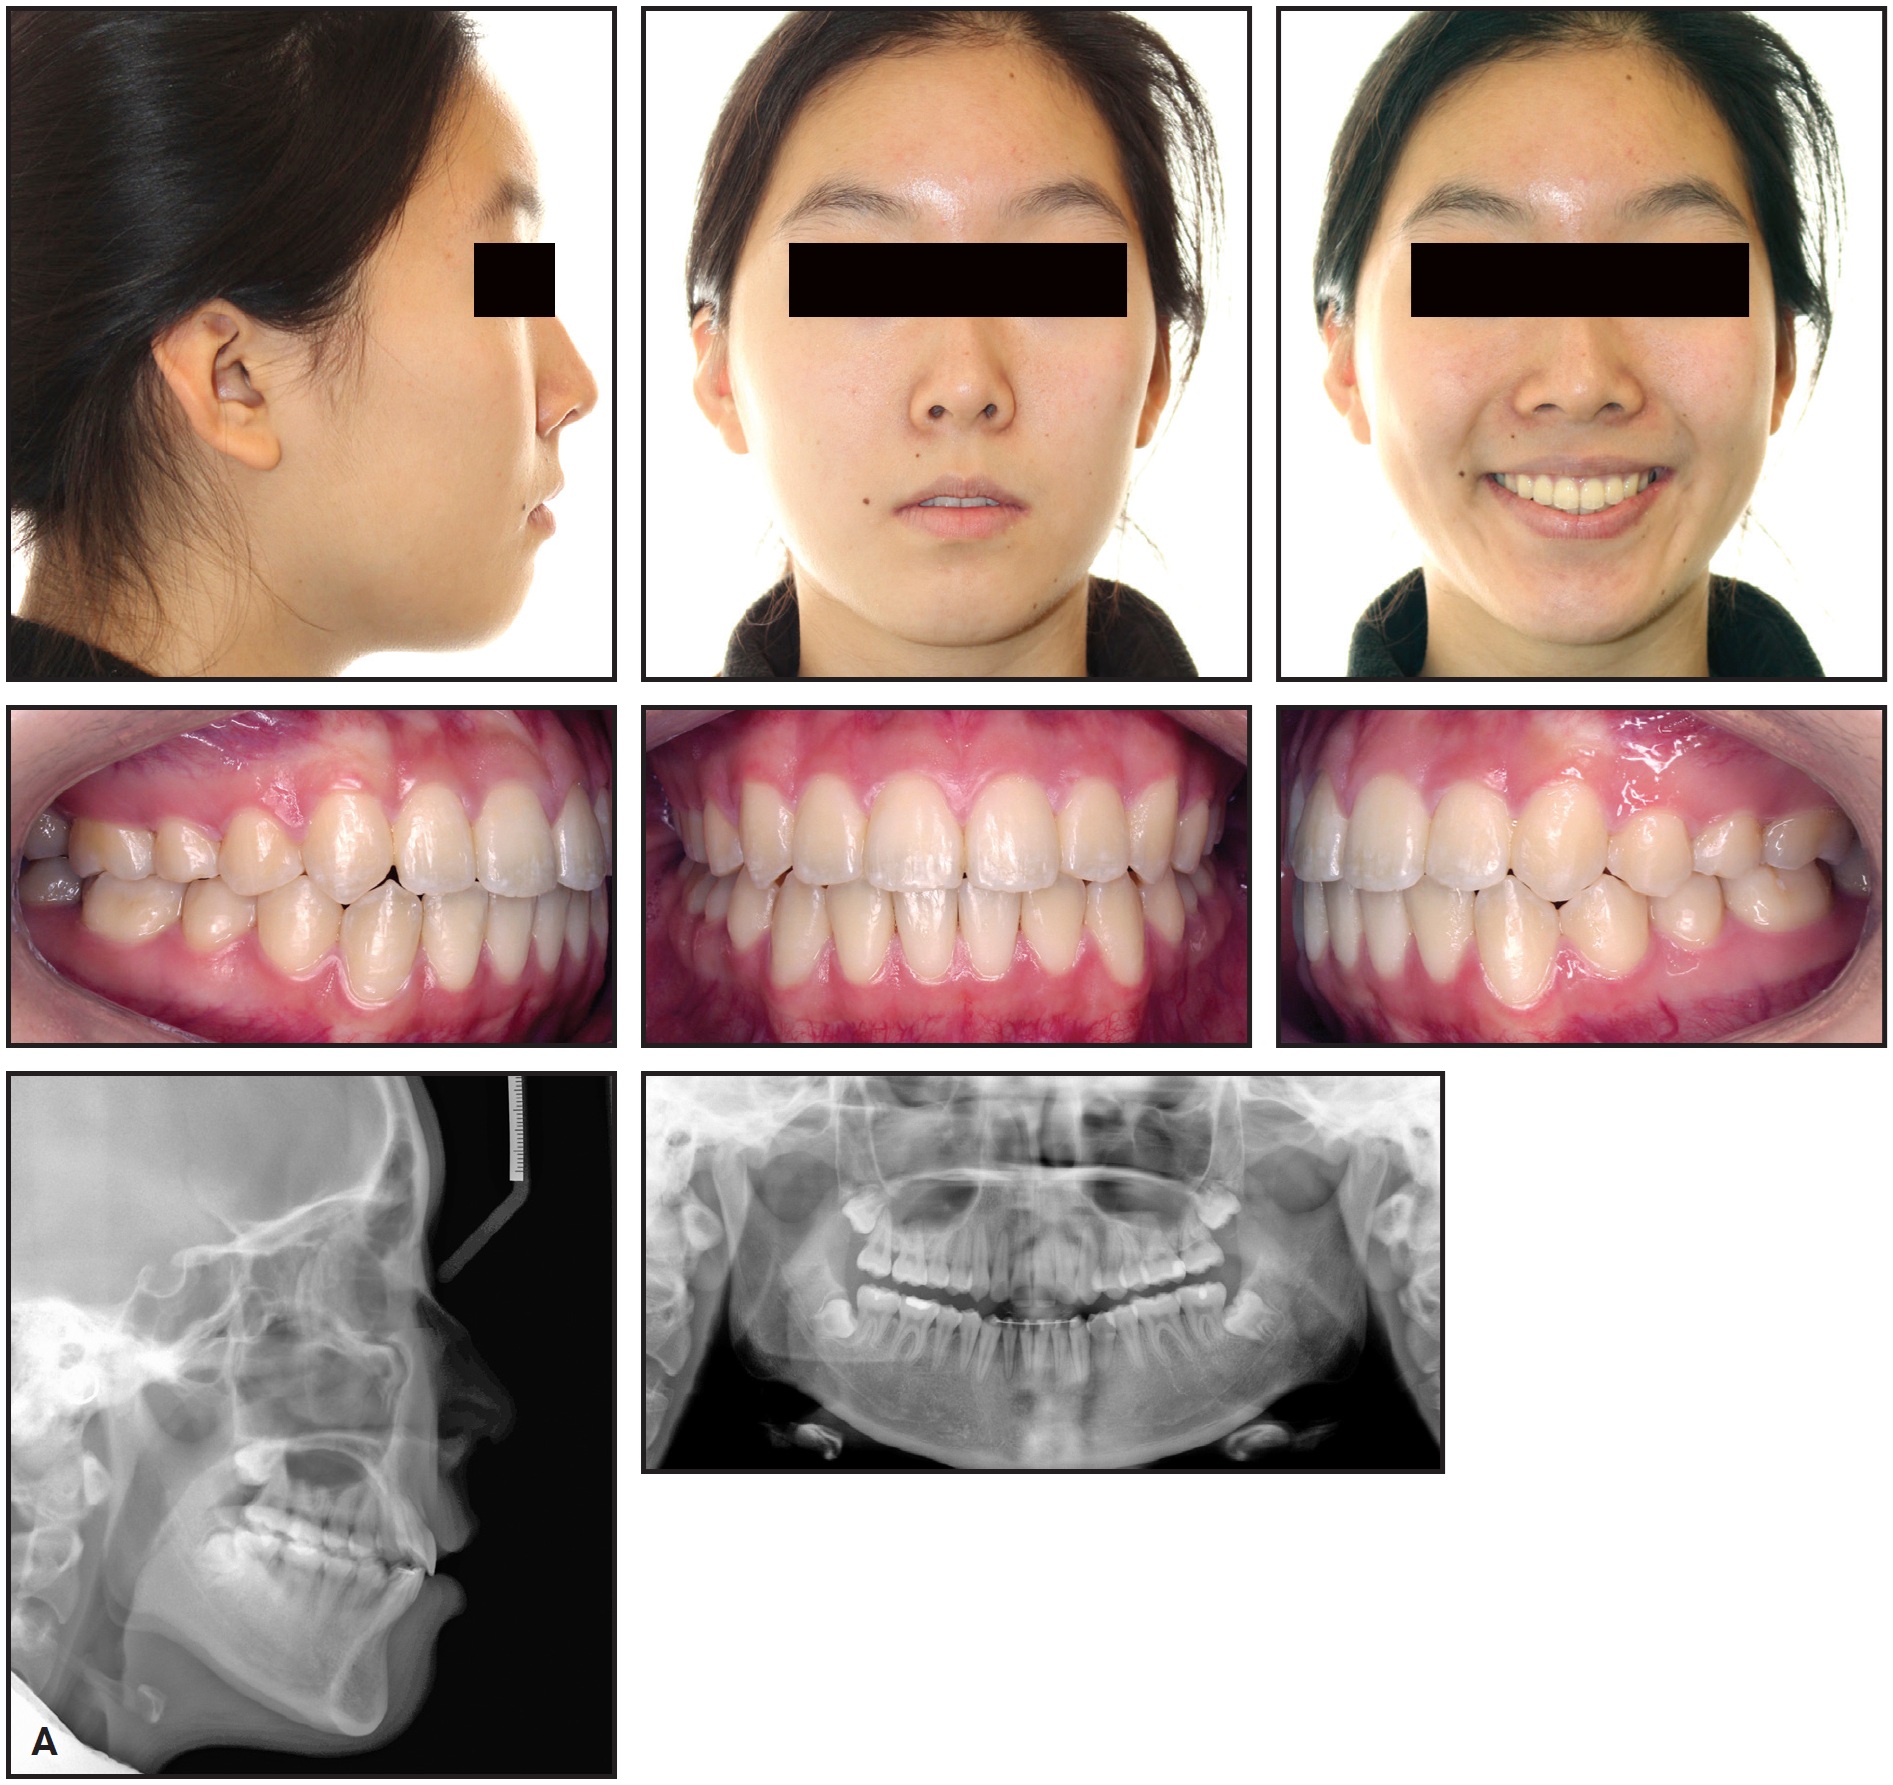

A 14-year-old female presented with the chief complaint of crowding (Fig. 1). She had a mildly convex facial profile with excessive lower anterior facial height and obtuse nasolabial and mentolabial angles, as well as a consonant smile arc with 1mm of gingival display in smiling. Intraoral examination found a 3mm overjet, a 1mm overbite at the incisor level, 2mm of open bite in the canine regions, and Class I molar and canine relationships.

Fig. 1 14-year-old female patient with excessive lower anterior facial height, hyperdivergent growth pattern, and Class I molar and canine relationships before treatment.

Cephalometric analysis indicated a slightly convex hard-tissue profile and mildly hyperdivergent growth pattern (Table 1). Vertically, the mandibular plane angle was slightly increased, and the distances from the upper and lower incisor apices to the palatal and mandibular planes were excessive. The upper and lower incisor inclinations were normal.